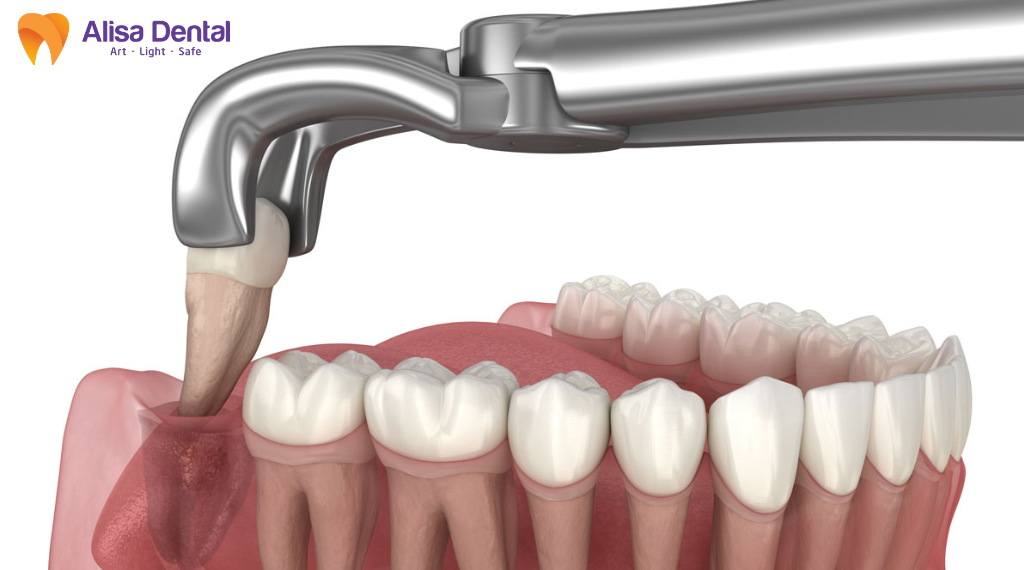

Răng khôn thường nằm sâu trong xương hàm, mọc lệch hoặc chèn ép răng kế cận, khiến quá trình nhổ phức tạp hơn so với răng thông thường. Việc phải bóc tách mô rộng, can thiệp vào xương hoặc chia nhỏ thân răng làm vùng tổn thương lớn hơn, kéo dài thời gian lành thương. Đây là yếu tố nền khiến nguy cơ viêm, sưng kéo dài hoặc khó hồi phục cao hơn, ngay cả khi quy trình được thực hiện đúng.